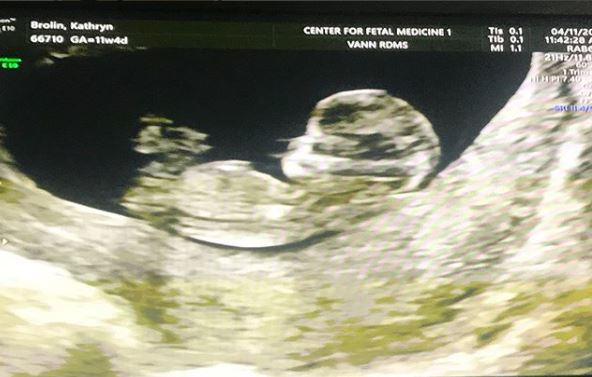

사진=조슈 브롤린 인스타그램

영화 ‘어벤져스: 인피니티 워’에서 타노스 역을 맡아 강렬한 인상을 남긴 배우 조슈 브롤린(50)이 가족 사랑을 드러냈다.

조슈 브롤린은 17일 자신의 인스타그램에 자신의 셋째 아이가 될 태아 사진을 올리며 가족사를 언급했다.

조슈 브롤린은 셋째가 될 태아의 초음파 사진을 올리며 “나는 고등학교를 졸업하고 2년 뒤에 아버지가 됐다. 나는 문제아였지만 아이가 내 삶에 기적을 가져다 줬다”고 설명했다.

이어 조슈 브롤린은 “곧 태어날 아이를 정말 사랑한다”면서 “태어나 줘서 너무나 고맙다”고 덧붙였다.